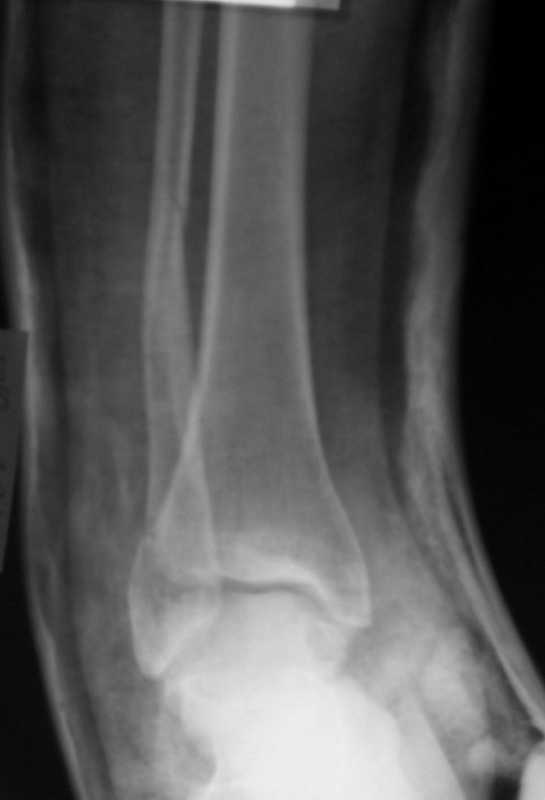

Вот рентгенконтроль на 7-е сутки после репозиции.

Стандартными снимками считается прямая, боковая и мортиз!!!, а так трудно гадать, насколько потеря длины малоберцовой. На боковом снимке не сопоставленный перелом медиальной лодыжки и перелом заднего края без смещения.

Очень жаль, что Вы так считаете и не прислушались к мнениям уважаемых коллег. Проблема этого голеностопного сустава не в "висячей" внутренней лодыжки, а ротированной и, возможно, укороченной малоберцовой кости. На снимках подвывиха как-буд-то бы нет, но таран ротирован и это в дольнейшем будет причиной раннего артроза.

нет нормальных проекций, трудно сказать как стоит м/б, если действительно неплохо - операция будет малотравматичной. синтезировав внутреннюю ложыжку, чего мы добьемся? гипс не снять, разработку не начать, даже если она на срастется или malreduction, это не большая проблема, а если развалится синдесмоз и неправильно срастется м\б это другая история

при таком нестабильном переломе удержать отломки в гипсе в имеющемся положении будет трудно, через 3 нед можно ожидать ухудшение репозиции, и тогда операция действительно будет более травматичной